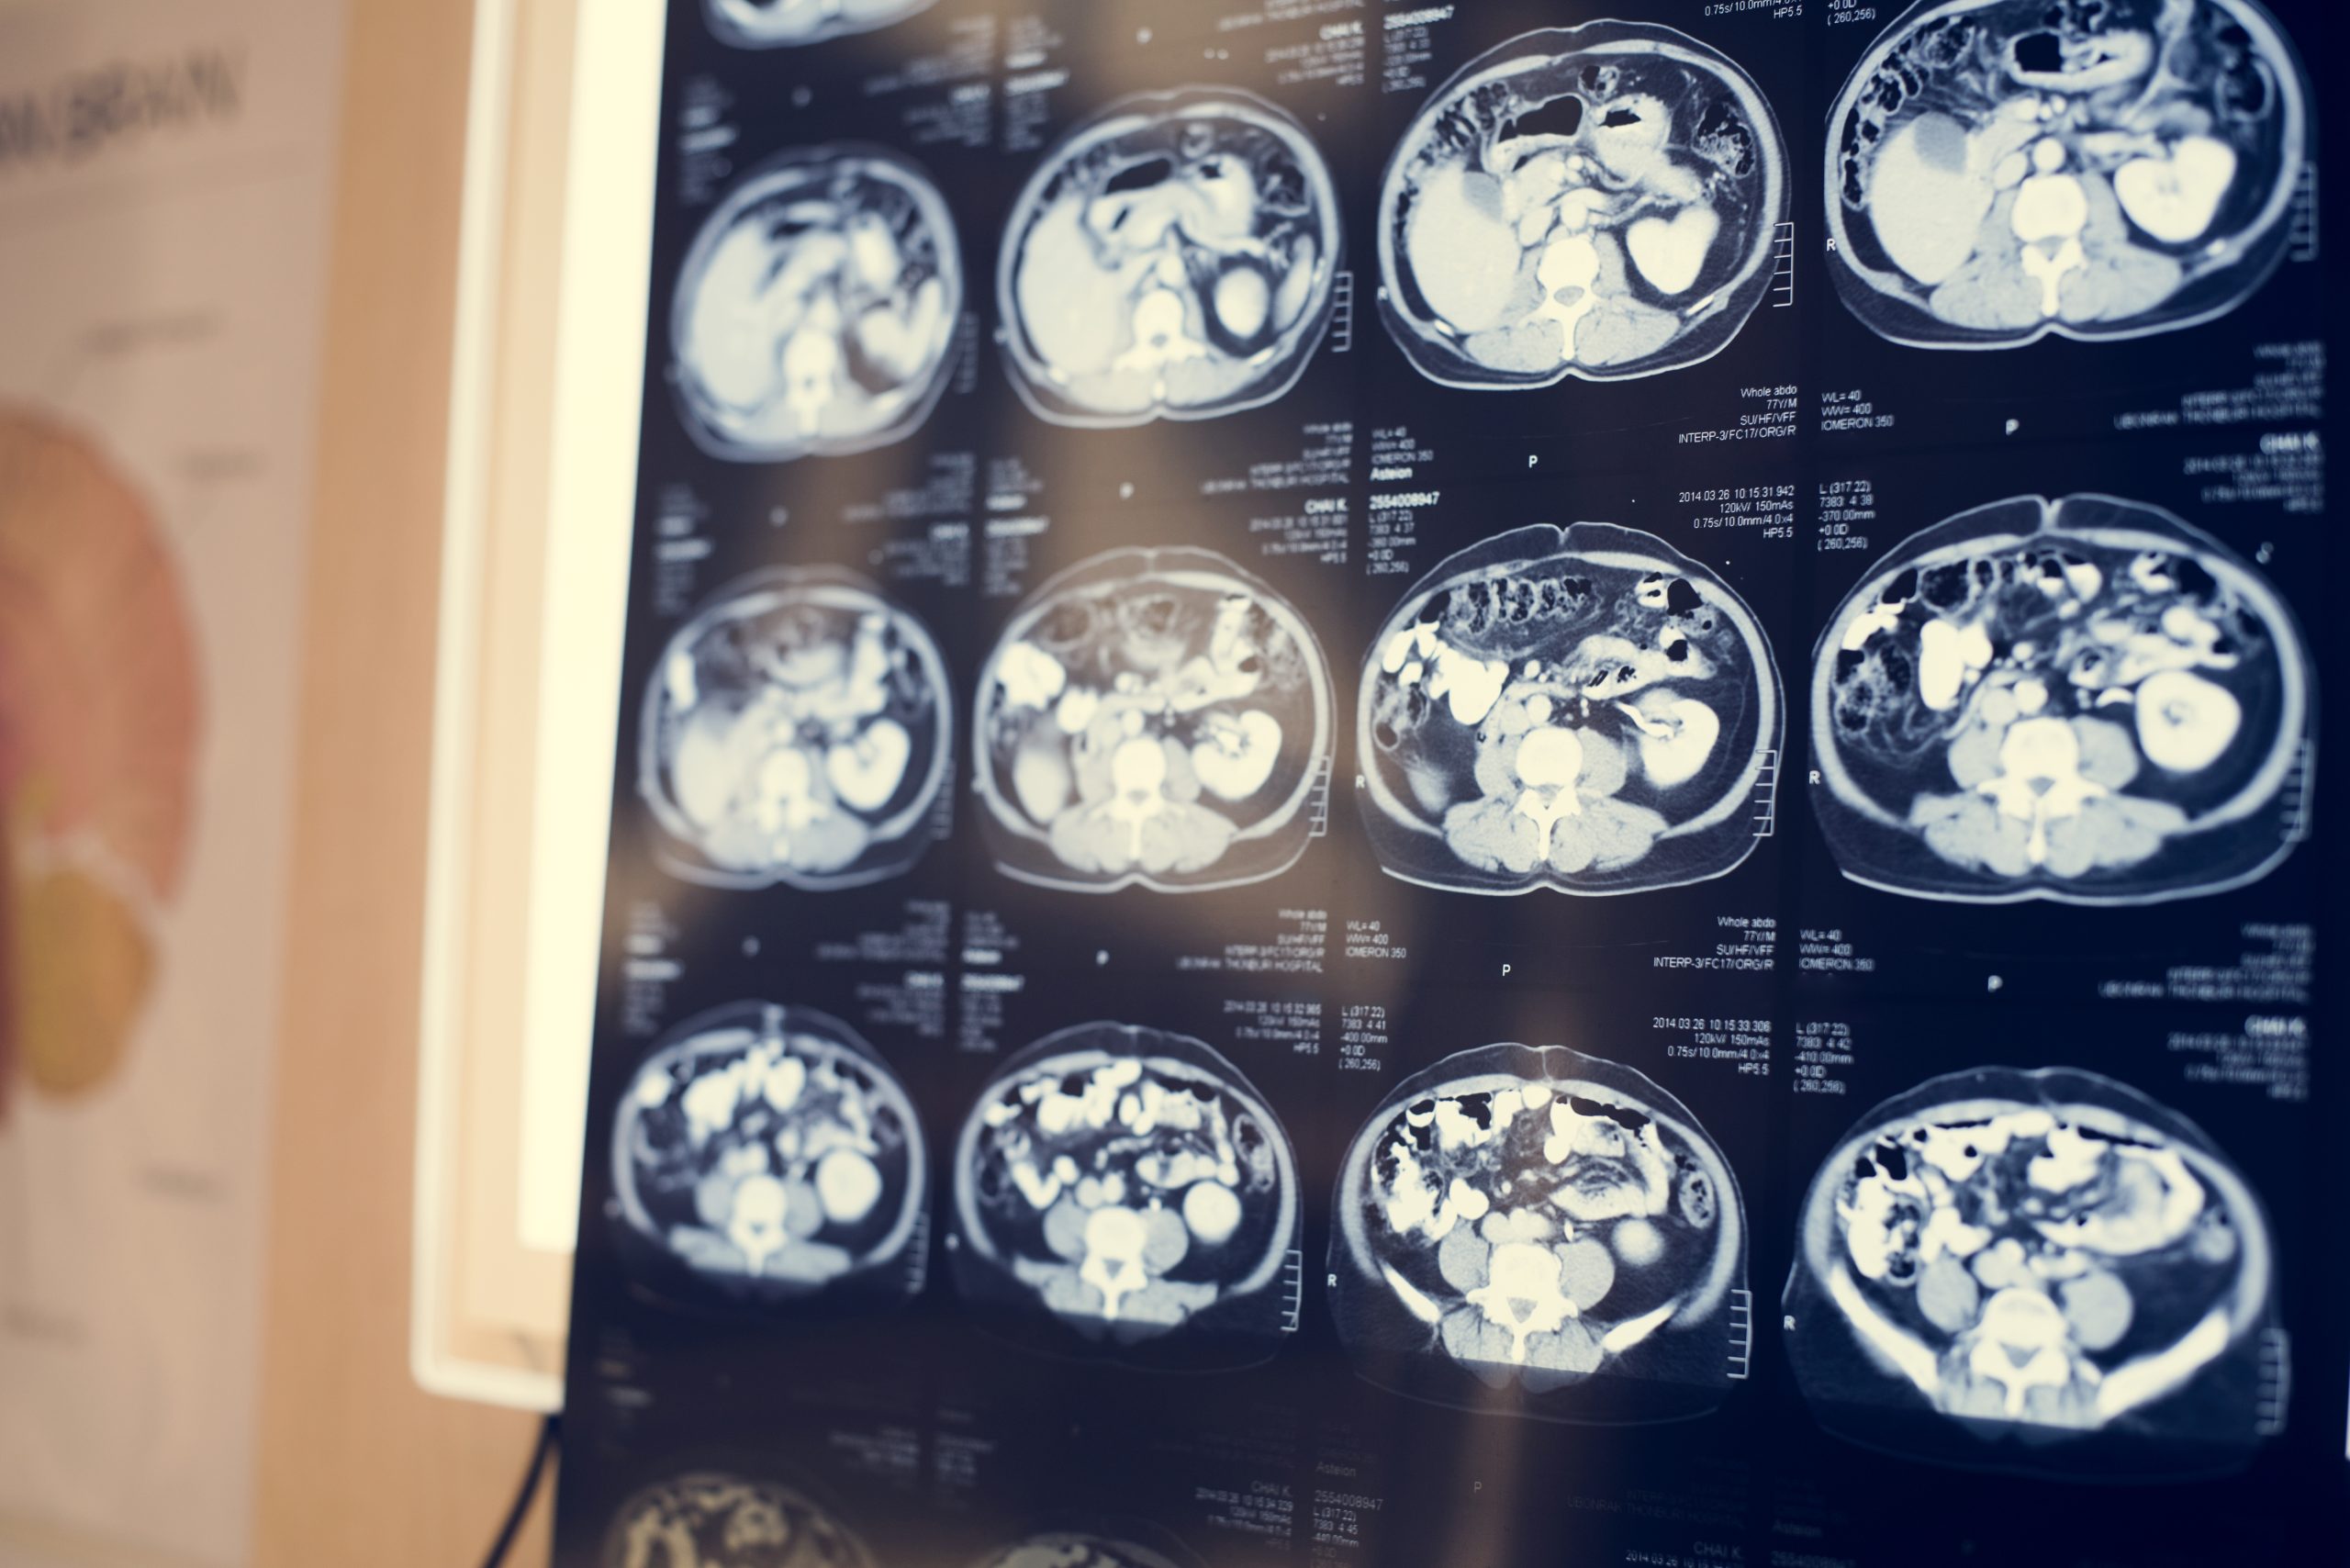

- Diagnostic imaging:

- Angiography and other diagnostic imaging provide detailed information about the location, size, and shape of the aneurysm.

- Computed tomography (CT) and magnetic resonance imaging (MRI) are complementary tools in the evaluation.